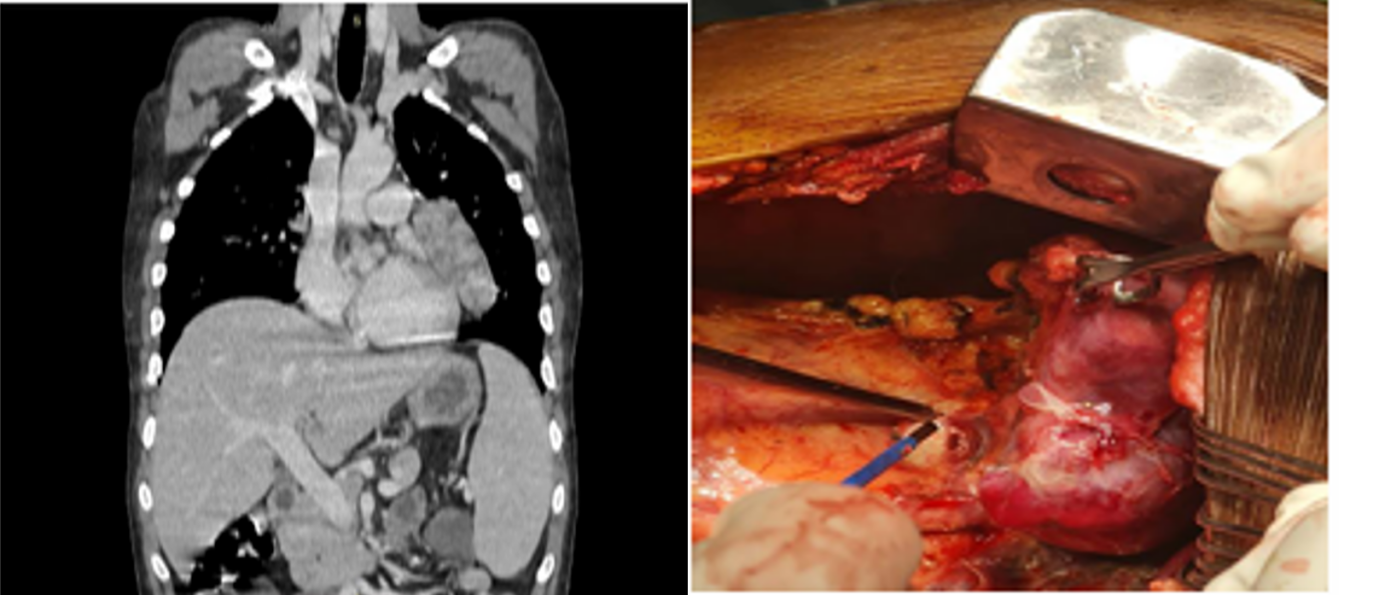

The patient was diagnosed with thymoma-associated multiorgan autoimmunity manifesting as adrenal insufficiency, inflammatory polyarthritis and mucocutaneous involvement. Additionally presence of persistent hypogammaglobulinemia with recurrent infections and chronic diarrhoea established the diagnosis of Good’s syndrome. The patient received sulfasalazine, mesalamine, H. pylori eradication therapy, corticosteroids, antidiarrheal therapy and multivitamins. Due to persistent diarrhoea and inflammatory symptoms, contrast-enhanced CT was performed revealing a heterogeneously enhancing mediastinal mass (Figure 2).

Figure 2: Imaging and intraoperative findings of anterior mediastinal mass – (Left) contrast-enhanced CT showing a well-defined lobulated anterior mediastinal mass, (Right) intraoperative view demonstrating surgical excision of the thymoma.

PET-CT confirmed a lobulated lesion in the left paracardiac and aortopulmonary region without metastasis.